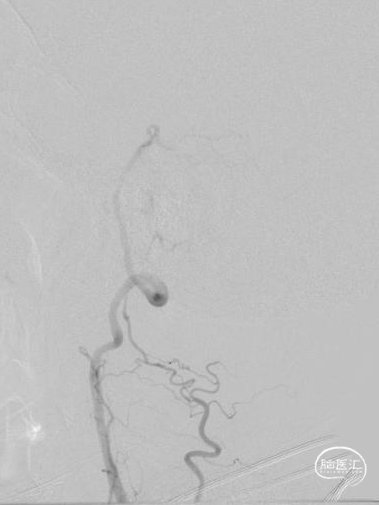

➢术后即刻影像

术中造影证实右椎纤细、右椎V4段可见微弱血流入基底动脉、左椎动脉开口闭塞、颈升动脉通过侧支循环向左椎V3供血并逆流至V1中段、左椎V4轻度狭窄;

对于该类病变我们的最优选择就是处理左侧椎动脉起始部。针对路径迂曲,其实当我们的微导丝通过病变到达左椎V3段时可明显看见血管拉直,迂曲的管径问题迎刃而解;

针对左椎V2长节段病变我们可以发现造影证实它既不属于狭窄也不属于夹层,而是颈升动脉血流逆流造成的术前影像的误判;

为减少血栓逃逸事件的发生及对椎动脉血管的刺激,我们选取了预留中间管+Syphonet®取栓支架作SWIM取栓准备。这款支架全程显影,且头端带网篮,对球囊扩张过程中的逃逸血栓有抓捕能力,且抗折性强,迂曲血管内能保持完整管腔,内置的支架输送导丝头端柔软可避免血管损伤,在该病例中发挥了保护伞的作用。